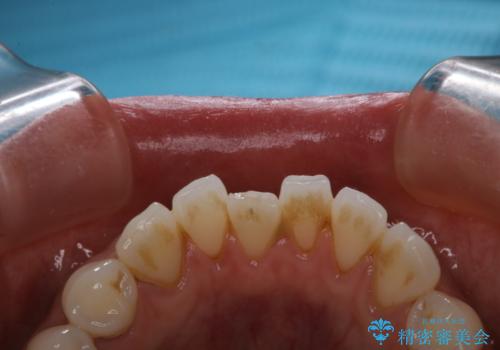

タバコによるヤニ、着色、歯の汚れをPMTC(60分コース)で除去。